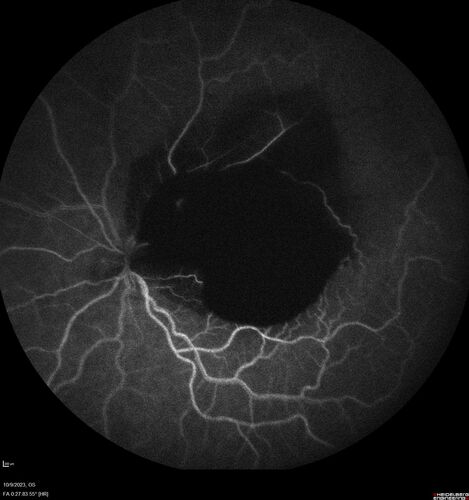

Ruptured Retinal Arterial Macroaneurysm - Submacular hemorrhage and BRAO

81 year old female with vision loss for a few days. Coumadin was high with INR at 3.1 VA 6/200